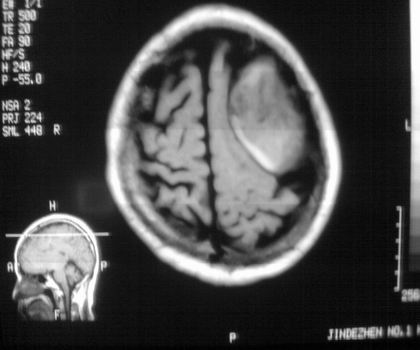

以下是引用影像孺子牛在2008-4-29 21:20:00的发言:[br]首先病变定位在脑外,根据ct密度及mri信号特征考虑慢性硬膜下血肿不连续环形钙化。

以下是引用周战梅在2008-4-29 23:12:00的发言:[br]脑外病变,蛛网膜下腔增宽,囊壁点状、环形钙化,增强扫描呈不均匀环状强化,考虑为囊性脑膜瘤可能性大,慢性脓肿、血肿机化、胆脂瘤不能除外。